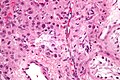

| LM | cytoplasmic vacuolization, cytoplasm -- clear to eosinophilic, +/-Reinke crystals (cylindrical crystalloid -- eosinophilic cytoplasmic bodies), +/-nucleoli common, round nuclei |

- Vacuolization (cytoplasm) - key feature.

- Cytoplasm - clear to eosinophilic - important.

- Usually eosinophilic.

- Reinke crystals - classic finding, usually not present.

- Cylindrical crystalloid eosinophilic cytoplasmic bodies.

- Nucleoli common.

- Round nuclei.